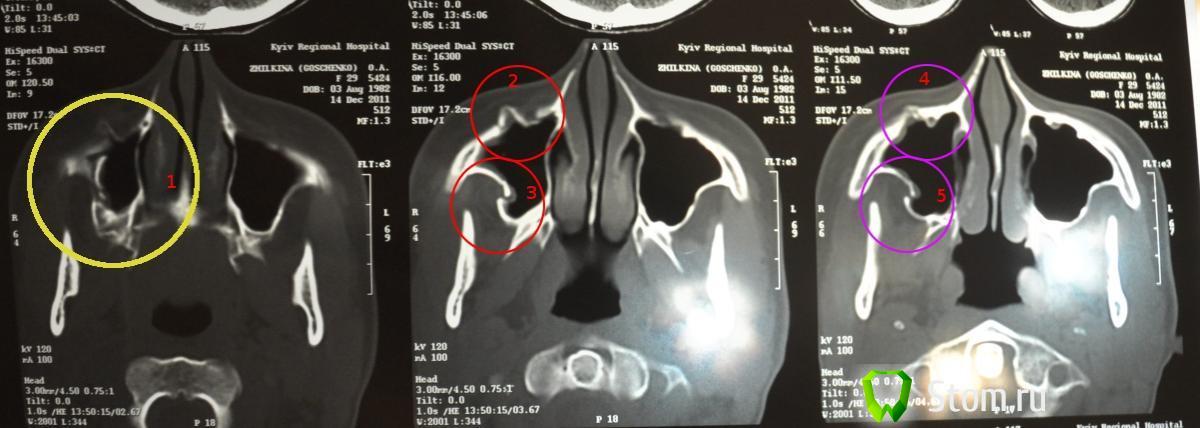

Oksana 29 Опубликовано 16 декабря, 2011 Поделиться Опубликовано 16 декабря, 2011 прочитала тему на этом форуме "перелом скуловой кости",у меня 12 дней назад была травма, перелом скуловой кости со смещением (дома потеряла сознание и упала на пол).Доставили меня по скорой помощи в поликлинику, сделали рентген.Первоначально сказал челюстно-лицевой хирург, что у меня "перелом правой скуловой кости без смещения" и сказал, что операция не нужна, но можно еще показать меня профессору в челюстно-лицевом отделении.Меня отпустили ,сделали укол линкоцидином (если правильно помню название) и взяли анализ крови и мочи.на следующий день я приехала на обход.Смотрели меня в палате, зав. отделением и профессор, сразу сказали что нужно делать операцию "репозиция скуловой кости".Врач меня убедил, что не нужно делать операцию, т.к. перелом незначительный и я согласилась , поверила его аргументам, написала заявление , что отказываюсь от операции.Изначально было онемение на лице от виска до верхней губы, рот открывался с трудом, была припухлость, но без гематомы (сказали, что меня спасло, что я сразу приложила лед к лицу в течение 2-х часов, конечно плотно обернула в ткань, чтобы не было слишком сильного холода).Онемение проходило, была сильная слабость, но в целом я соблюдала рекомендации врача, уколы линкоцидина дважды в сутки и не спала на правой части лица.Спустя 10 дней я обеспокоилась онемением, которое меня не покидало на верхней губе, остальная часть восстановила чувствительность, намного лучше стало и сошла припухлость.Поехала к нейрохирургу в другую больницу, меня направили на КТ.Результаты не показали патологии, воспаления либо сотрясения мозга, но было видно смещение скуловой кости, о котором не написали в заключении...(что не понятно).Направили в челюстно-лицевой отдел, в этой же областной больнице меня направили к челюстно-лицевому хирургу, и показали зав. отделением. Сразу сказали что нужна операция, что повреждена орбита глаза и гайморова пазуха.. я решила не ложиться сразу под нож, т.к. слышала негативные отзывы об этом зав.ч/л отделением.Смотрели меня также от медицинского института, зав.кафедрой ч/л хирургии, сказали, что не нужно уже ничего делать.Я уже совсем запуталась, поехала на консультацию в главный военный госпиталь чтобы получить независимую оценку, принимал меня нач.клиники челюстно-лицевой хирургии и стоматологии, посмотрел КТ, прощупал поврежденную кость ,сказал что смещение 0,5 см, будет заметно со временем на лице еще больше ассиметрия, и что нужно делать операцию, придется уже (т.к. 12 дней со дня травмы) ломать кости и ставить их на место, с помощью титановой пластины фиксировать и через год можно пластину удалить....Обращаюсь к тем, кто может мне подсказать, прилагаю КТ (скан) -нужно ли мне теперь ломать кости, чтобы заново поставить их на место, или это совершенно не нужно?на КТ врачи обращали внимание только на "3" и "5" (выделено уже мной).Правда ли по КТ что такое смещение - 0,5 см? Ссылка на комментарий

ПалСаныч Опубликовано 17 декабря, 2011 Поделиться Опубликовано 17 декабря, 2011 (изменено) Оксана, я так понимаю(судя по сканам) Вы обращались в киевский главный военный госпиталь )))На наше суждение Вы представили вообще 3 скана и судить однозначно по Вашему случаю на основании столь скудной информации невозможно. По этим сканам можно лишь сказать, что линия перелома проходит именно в месте расположения нерва, который отвечает за чувствительность обозначенной Вами области. Возвратится чувствительность после операции или нет вообще сказать невозможно, это зависит от того, насколько поврежден нервный пучек, зажатый между отломков. А еще,забыл, за 12 дней кости не срастаются полностью Изменено 17 декабря, 2011 пользователем ПалСаныч Ссылка на комментарий

Aldo Rain Опубликовано 17 декабря, 2011 Поделиться Опубликовано 17 декабря, 2011 Я больше склоняюсь к операции, завал скул кости очевиден, останется асимметрия лица и онемение. Как рот открывается сейчас? Ссылка на комментарий

kriokov Опубликовано 17 декабря, 2011 Поделиться Опубликовано 17 декабря, 2011 Оксана, я так понимаю(судя по сканам) Вы обращались в киевский главный военный госпиталь )))На наше суждение Вы представили вообще 3 скана и судить однозначно по Вашему случаю на основании столь скудной информации невозможно. По этим сканам можно лишь сказать, что линия перелома проходит именно в месте расположения нерва, который отвечает за чувствительность обозначенной Вами области. Возвратится чувствительность после операции или нет вообще сказать невозможно, это зависит от того, насколько поврежден нервный пучек, зажатый между отломков. А еще,забыл, за 12 дней кости не срастаются полностью+1, ситуация не простая для оценки только по трем срезам, Скуловая участвует в образовании нижней и боковой стенок глазницы, здесь не по интернету а очно разбираться надо. Если рот не открывается до конца, или как бы "двоение в глазах" есть, оперироваться придется. Ссылка на комментарий